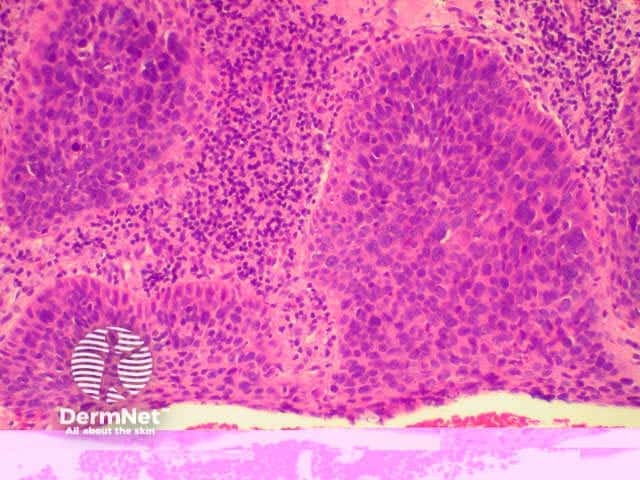

The histological characteristics of keratinocytic tumours are illustrated below.

Squamous cell carcinoma

SCC presents as an irregular keratinous nodule or a firm erythematous plaque, and frequently ulcerates. Histologically, atypical keratinocytes proliferate within the dermis.